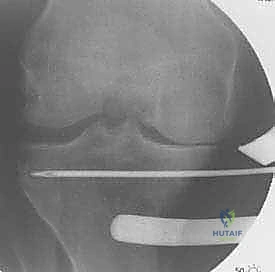

تُعد الأشعة السينية (X-rays) الممتدة من الحوض إلى الكاحل (Scanogram) ضرورية جداً لحساب زاوية التقوس بدقة وتحديد مقدار التعديل المطلوب جراحياً.

قبل العملية، يتم قياس زوايا الركبة بدقة متناهية. كل درجة من درجات التعديل يتم حسابها مسبقاً.

استخدام التخطيط الرقمي يضمن عدم حدوث تصحيح مفرط (Over-correction) أو تصحيح ناقص (Under-correction)، وهو ما يميز الجراح الخبير عن غيره.

3. إجراء القطع العظمي (The Osteotomy):

باستخدام أدوات دقيقة ومناشير جراحية متطورة، يتم عمل قطع غير مكتمل في عظمة الساق. هناك طريقتان رئيسيتان:

* الشق المفتوح (Opening Wedge): يتم فتح العظم من الداخل وإضافة طعم عظمي (صناعي أو طبيعي) لملء الفراغ وتعديل الزاوية. وهي الطريقة الأكثر شيوعاً حالياً.

* الشق المغلق (Closing Wedge): يتم إزالة إسفين (مثلث) صغير من العظم من الجهة الخارجية وإغلاق الفراغ.

4. تعديل المحور:

يتم فتح العظم تدريجياً وببطء شديد حتى الوصول إلى الزاوية التي تم حسابها في التخطيط الرقمي قبل الجراحة.